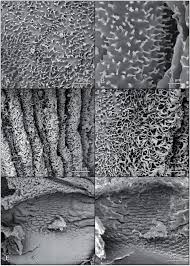

Metabolite Analysis And Histology On The Exact Same Tissue Comprehensive Metabolomic Profiling And Metabolic Classification Of Prostate Cancer Scientific Reports

Metabolite Analysis And Histology On The Exact Same Tissue Comprehensive Metabolomic Profiling And Metabolic Classification Of Prostate Cancer Scientific Reports from media.springernature.com